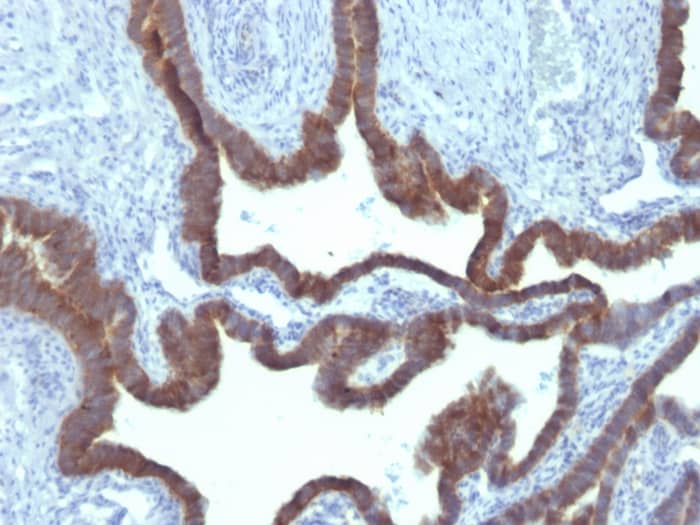

Formalin-fixed, paraffin-embedded human Ovarian Carcinoma stained with Cytokeratin 7 Antibody (KRT7/903) - Azide and BSA Free

Cytokeratin 7 is a basic cytokeratin, which is found in most glandular and transitional epithelia but not in the stratified squamous epithelia. Keratin 7 is expressed in the epithelial cells of ovary, lung, and breast but not of colon, prostate, or gastrointestinal tract. Antibody to cytokeratin is useful in distinguishing ovarian carcinomas (keratin 7+) from colon carcinomas (keratin 7-).

• Immunohistochemistry-Paraffin 1 - 2 ug/ml

Immunohistochemistry (Formalin-fixed): 1-2ug/ml for 30 minutes at RT. Staining of formalin-fixed tissues requires heating tissue sections in 10mM Tris Buffer with 1mM EDTA, pH 9.0, for 45 min at 95C followed by cooling at RT for 20 minutes.